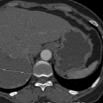

序列 临床意义 图像

Abd Aorta MIP

显示腹部主动脉及其主要分支血管的起源.走形及其它的形态